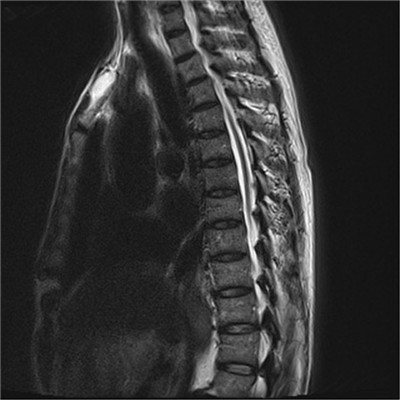

患者张某,男,69余,患者以“腰痛伴双下肢抽痛5年,摔伤后加重伴行走困难6天”在当地诊断为腰椎滑脱伴椎管狭窄(图1),转入我科拟行手术治疗,入院后完善检查,发现患者有广泛严重的胸椎黄韧带骨化伴不全瘫(图2),钙化范围涉及了胸2至腰2节段,且很多节段压迫极其严重(图3),原本相当于大拇指粗细的椎管,被钙化的黄韧带硬生生挤成了一条缝。

图2 胸椎